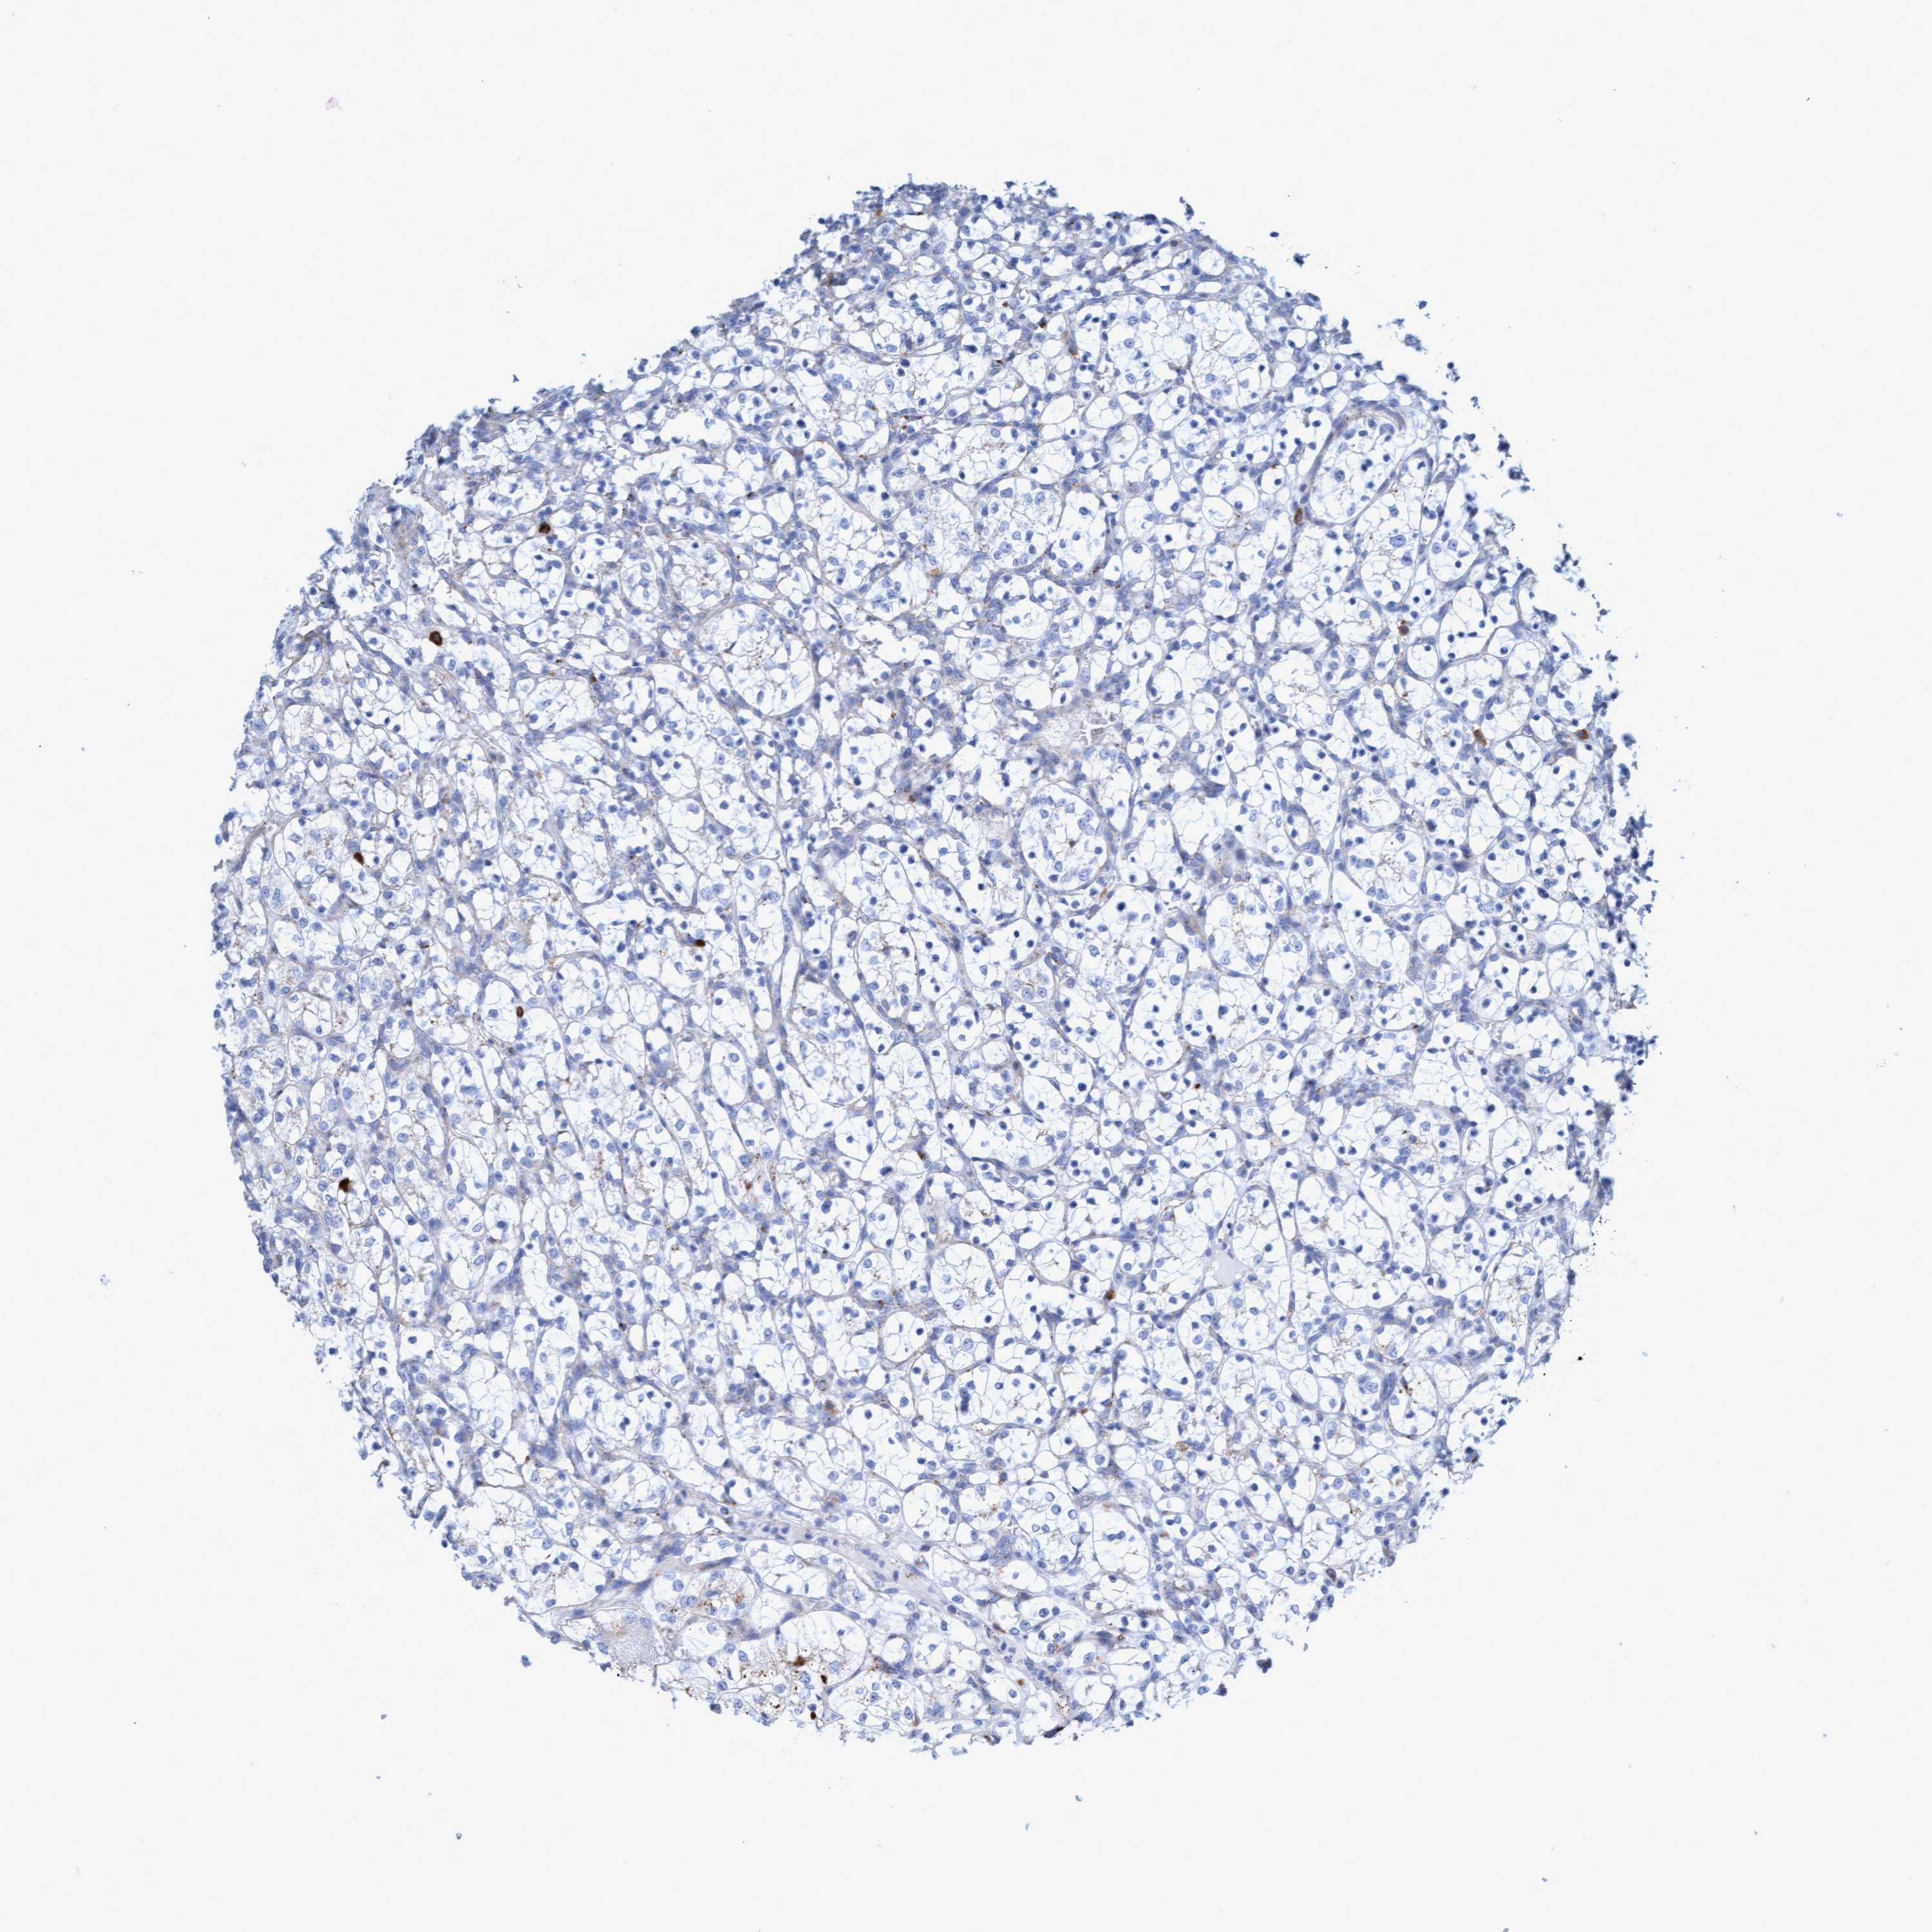

Average pTPM 16.6

Number of samples 64